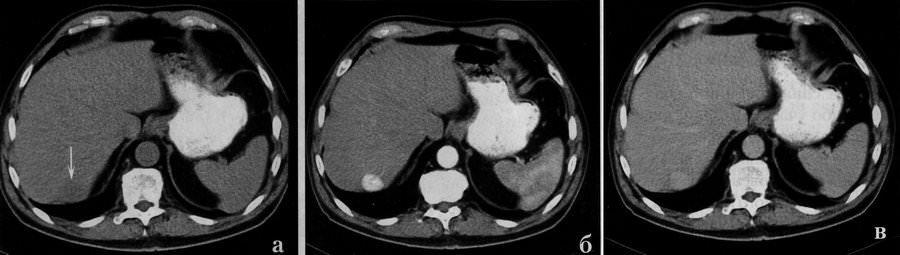

Аденома печени. При нативной КТ (а) в 7 сегменте определяется неотчетливо определяется слегка гиподенсивное образование, которое в артериальную фазу контрастного усиления (б) интенсивно окрашивается. В венозную фазу (в) сохраняется незначительно выраженная гиперденсивность.

Маленькие аденомы на нативных компьютерных томограммах выявляются с трудом, они изоденсивны с паренхимой печени. По характеру распределения контрастного вещества при болюсном усилении аденома мало отличается от узловатой гиперплазии печени. Также как узел гиперплазии, опухоль показывает существенное усиление в артериальную и раннюю венозную фазы (фото КТ выше).